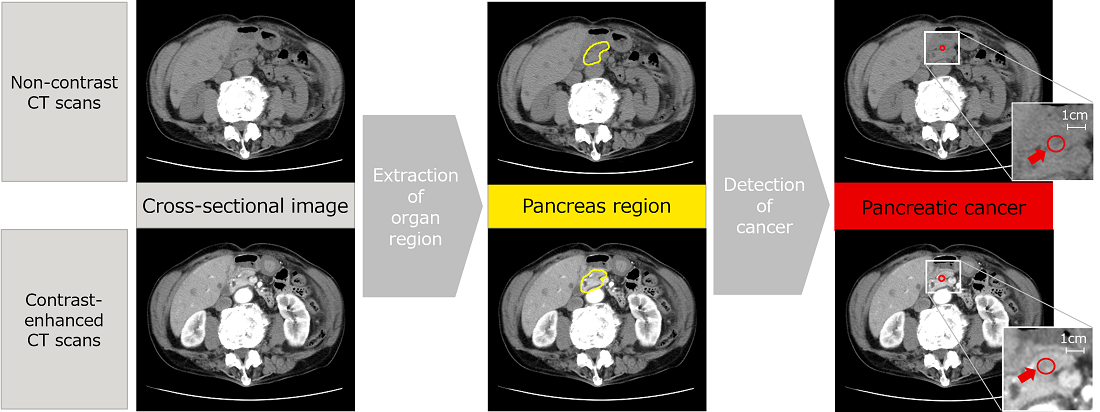

AI technology to detect pancreatic cancer from non-contrast CT scans -- Contributing to a healthier society --

Pancreatic cancer is a disease that is difficult to detect in the early stages, and it has proven difficult to establish a technology capable of identifying cancers beyond all doubt and thereby increasing the opportunities for detection in the initial stages.

To address this problem, Fujitsu has been collaborating since April 2022 with the Southern TOHOKU General Hospital (*10) and others to promote the development of AI technology to detect pancreatic cancer from non-contrast CT scans, such as those widely carried out during general health checks and similar procedures.

Due to the low levels of contrast in non-contrast CT scans, it has always been difficult to identify the location of the pancreas and detect cancers. So, Fujitsu has used AI to develop a technology that estimates the continuity across adjacent cross-sectional scans, taking into account the patient’s anatomy. It automatically conducts three-dimensional analysis in areas with strong continuity in the images and planar analysis in areas with weak continuity. The results of evaluations of the CT scans from the Southern TOHOKU General Hospital show that locations where cancer is suspected in the pancreas area were successfully detected with 90% accuracy.

This AI technology is the result of the use of converging technologies (*11) that integrate Fujitsu’s image analysis technology with the clinical observations made by the Southern TOHOKU General Hospital, and is likely to make a significant contribution to improving the early discovery of pancreatic cancer. In 2023, this technology was unveiled to over 20,000 physicians and other participants at JDDW 2023 (*12), where it demonstrated the advanced level of the technology addressing social needs.

Detection of suspected pancreatic cancer using the newly developed technology